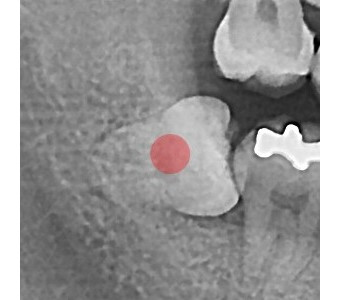

以成果证明实力。

国际摩牙齿科

真实临床案例